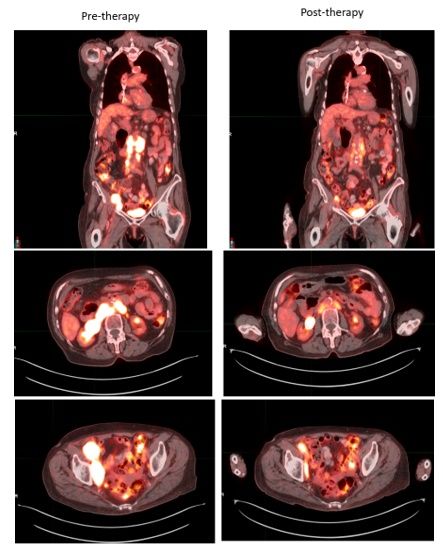

A male in his 60s with a history of morbid obesity, status post gastric bypass, was incidentally found to have bulky retroperitoneal lymph nodes upon CT imaging done during workup of suspected GI bleeding. A retroperitoneal core needle biopsy came back consistent with follicular lymphoma, grade 3A. Given that he had bulky disease, he received 6 cycles of R-CHOP and achieved a complete remission. About 18 months later, surveillance imaging identified progressive disease with new left inguinal adenopathy and a T4 paraspinal mass, which were 18F-Fluorodeoxyglucose (FDG)-avid on PET imaging with a standardized uptake value (SUV) of 7.8. A biopsy from the inguinal lymph node was consistent with relapsed follicular lymphoma, grade 1-2. He subsequently underwent radiation to the T4 paraspinal mass followed by R2 and achieved complete remission again. However, 13 months afterwards, he complained of left lower extremity pain and was found to have relapsed disease with bulky FDG-avid pelvic adenopathy on PET imaging in addition to other FDG-avid adenopathy above and below the diaphragm. The highest SUV was less than 10 in the pelvic area and a pelvic lymph node biopsy showed follicular lymphoma without evidence of transformation to an aggressive lymphoma. At that point CAR T-cell therapy was discussed, but the patient lived more than 2 hours away from the medical center and did not have a caregiver, which was a prerequisite to getting CAR T-cell therapy. EZH2 testing was performed on a prior lymph node biopsy which was positive for an EZH2 mutation. He was initiated on oral tazemetostat and achieved a partial remission and remained without progression at his last follow up visit 18 months later.